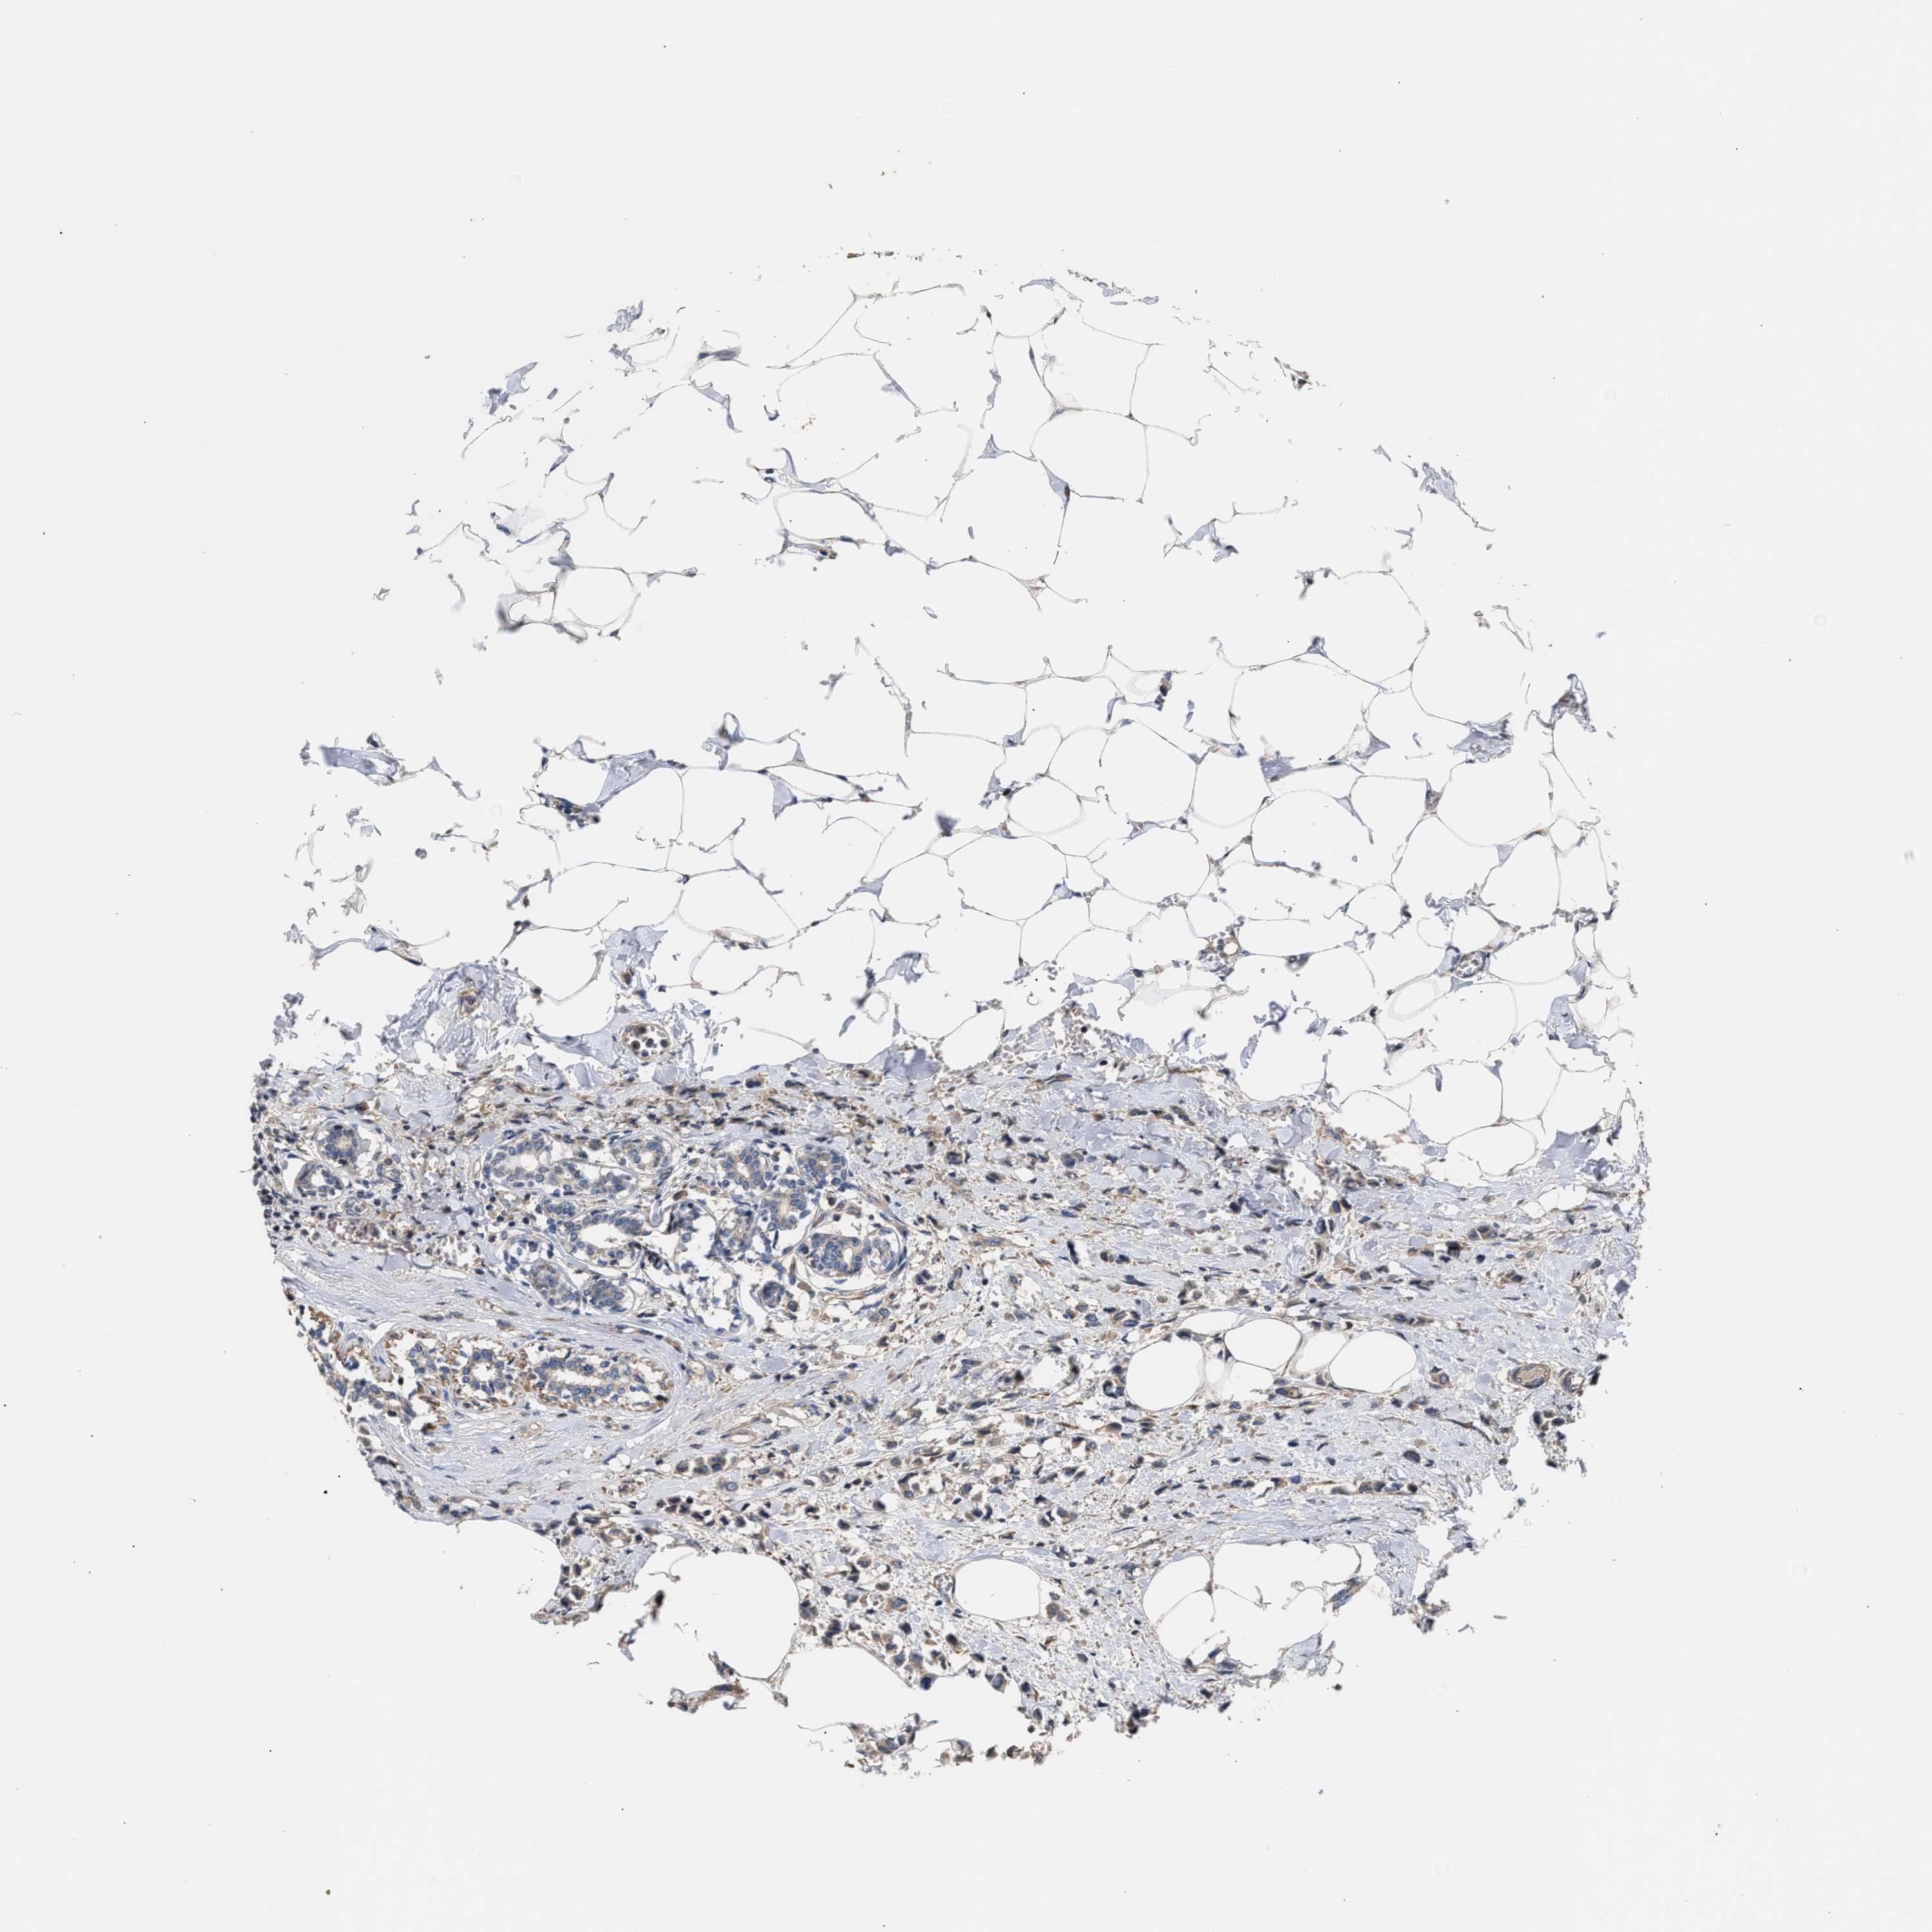

CANCER BREAST CANCER Show tissue menu

BRCA TCGA BRCA VALIDATION PROTEIN EXPRESSION